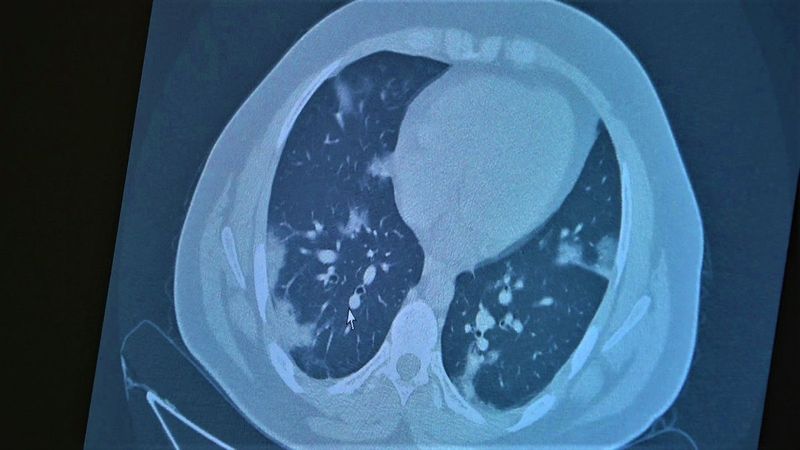

Çocukların akciğer tomografilerini inceleyen Özkaya, açıklamalarına şu ifadeler ile devam etti:

“11 yaşında kovid pozitif bir öğrencimiz, yüksek ateş ve nefes darlığı ile bize geldi. Ciddi akciğer tutulumu var. Geçen yıl ‘bu çocuklar hastalıktan etkilenmiyor’ diyorduk. Bu çocukta görüyorsunuz buzlu camlar ve konsolidasyon alanlarla seyrediyor. Geçen yıl bu şekilde çok çocuk görmüyorduk. Önümüzdeki aylarda bu şekilde devam ederse çocuklarımızı kaybetmeye bile başlayabiliriz.